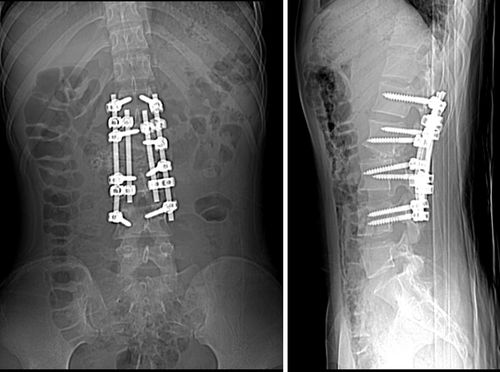

强直性脊柱炎后凸畸形

男14岁,先天性脊柱侧后凸

先天性脊柱侧弯畸形 l3椎体半椎体畸形 腰椎侧后突畸形